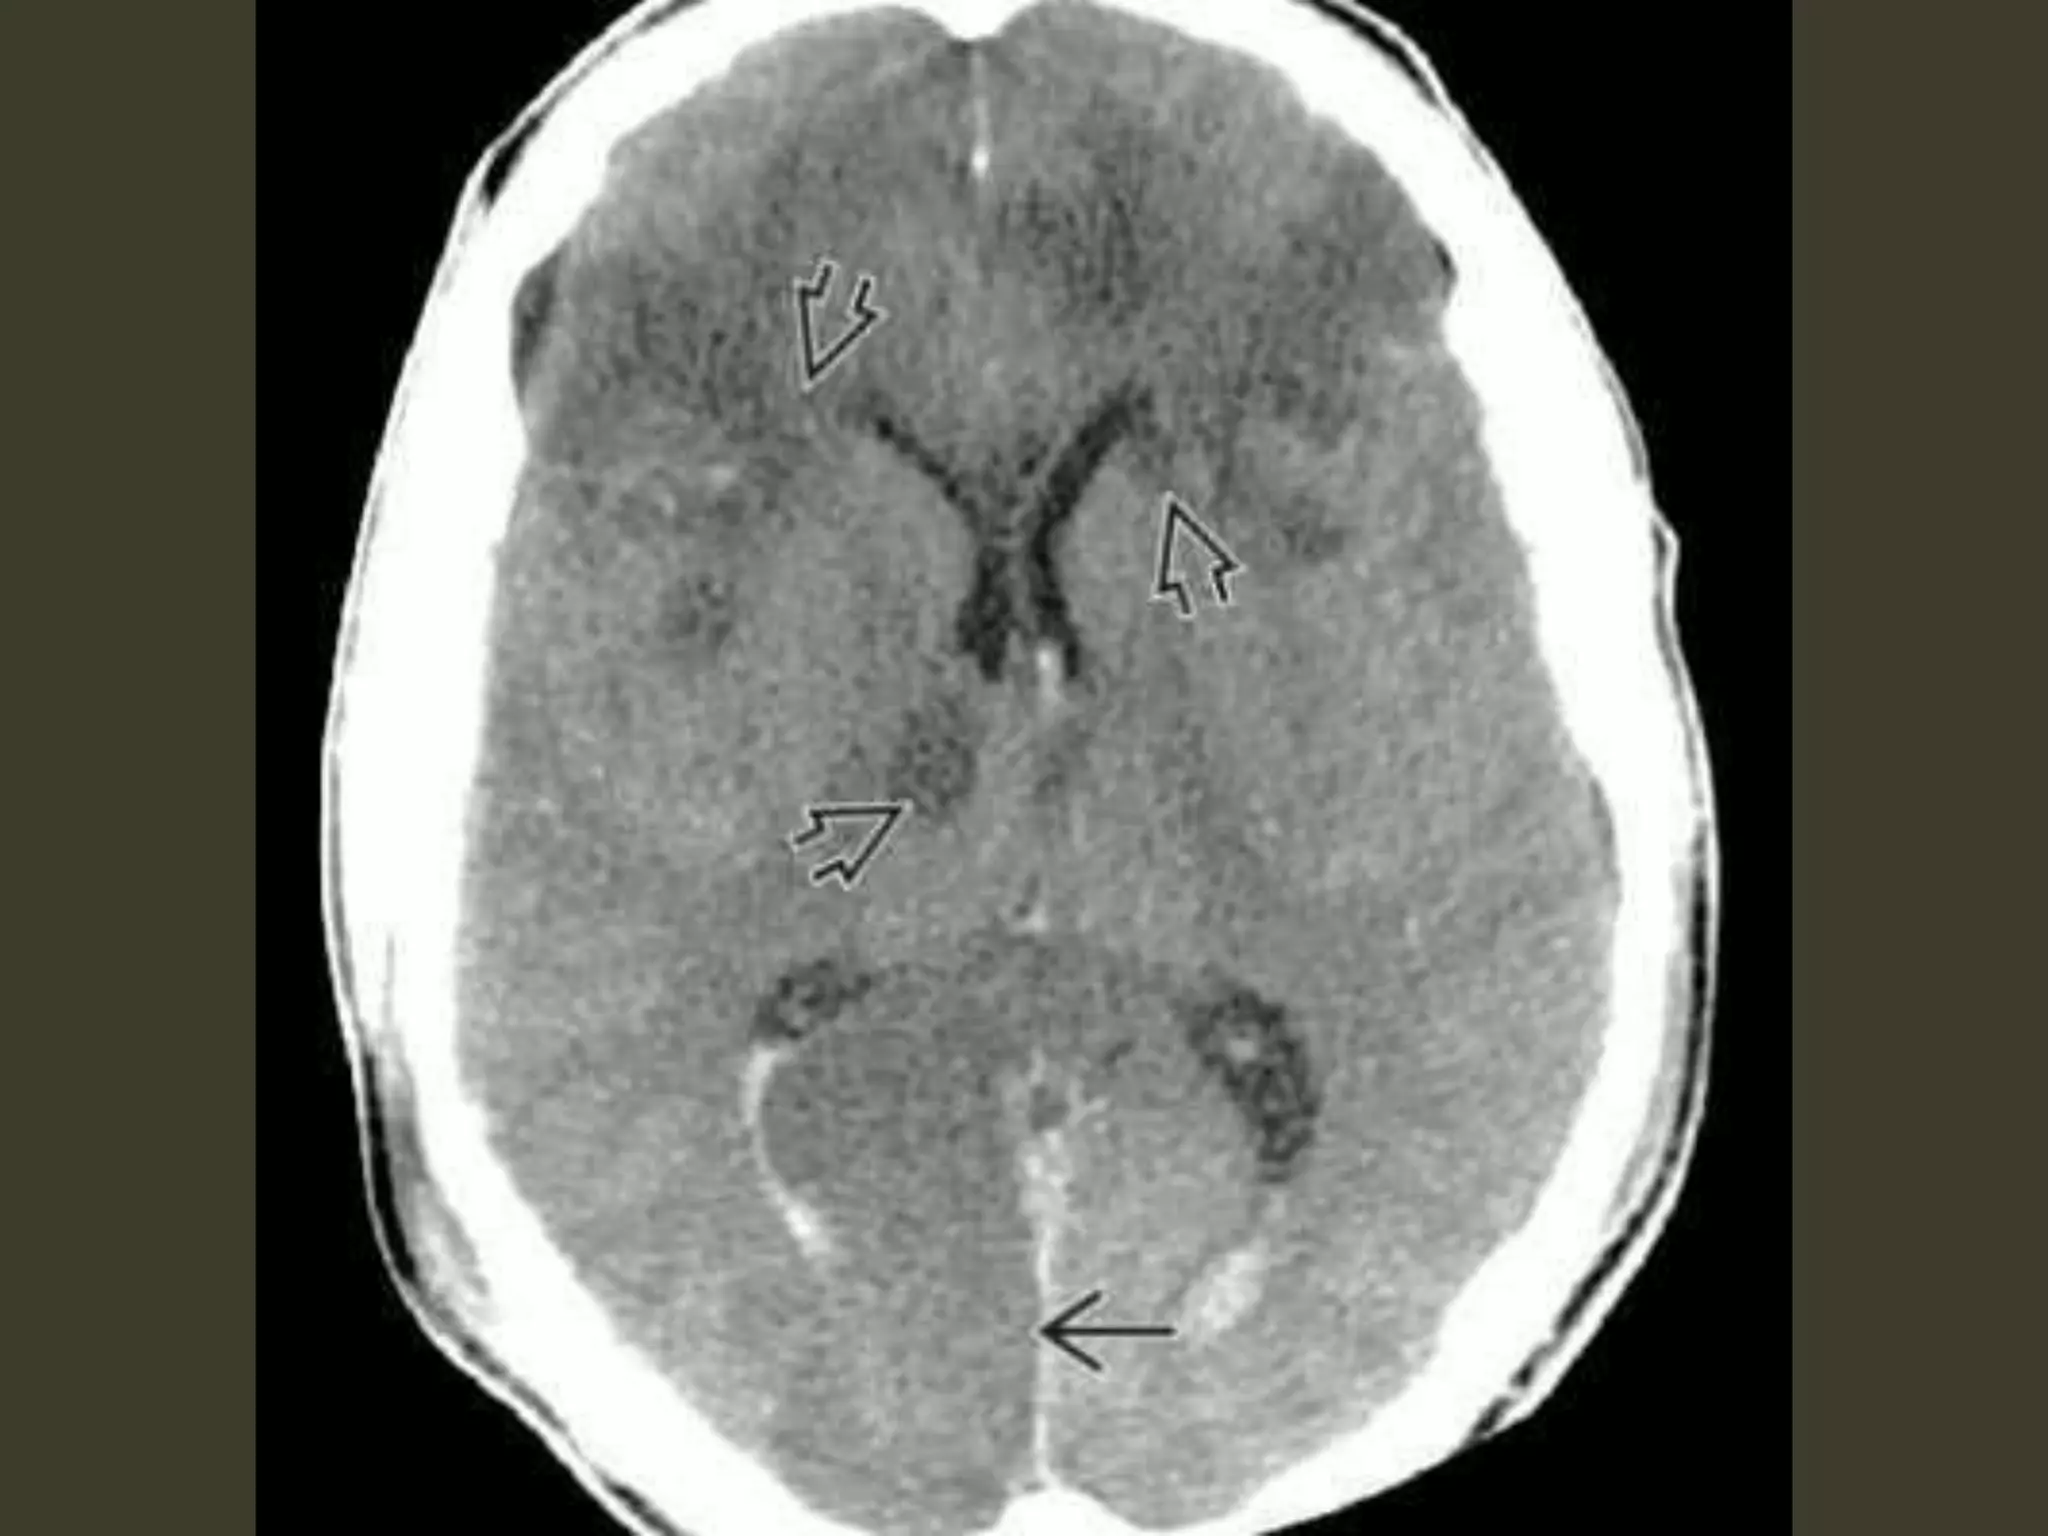

Descending transtentorial

herniations• the second most common

• a hemispheric mass

• initially produces subfalcine herniation

• As the mass effect increases,

the uncus of the temporal lobe is pushed medially

begins to encroach on the suprasellar cistern

hippocampus follows

hippocampus effaces the ipsilateral quadrigeminal

cistern

both the uncus and hippocampus herniate inferiorly

through the tentorial incisura

herniation

• Unilateral

• Bilateral ;"central“

unilateral DTH: imaging

early

uncus is displaced medially

Ipsilateral aspect of the suprasellar cistern

effaced

Ipsilateral prepontine + cerebellopontine angle

cistern enlarged

As DTH increases

hippocampus also herniates

medially

quadrigeminal cistern

compression midbrain pushed

toward the opposite side of the incisura

severe cases

entire suprasellar and quadrigeminal cisterns

are effaced.

The temporal horn can even be displaced almost

into the midline

bilateral DTH

both hemispheres become swollen

the whole central brain is flattened against the

skull base

All the basal cisterns are obliterated

hypothalamus and optic chiasm are crushed

against the sella turcica

Complications

• CN III (oculomotor) nerve compression

– CN III palsy

• PCA occlusion as it passes back up over the

medial edge of the tentorium

– secondary PCA (occipital) infarct

Kernohan notch

• As the herniating temporal lobe pushes the

midbrain toward the opposite side of the

incisura

– contralateral cerebral peduncle is forced

against the hard edge of the tentorium

• Pressure ischemia 🡪 ipsilateral hemiplegia

– the "false localizing" sign

Duret hemorrhage

"Top-down" mass effect displaces the midbrain

inferiorly

closes the midbrain-pontine angle

Perforating arteries from basilar artery

are compressed and buckled